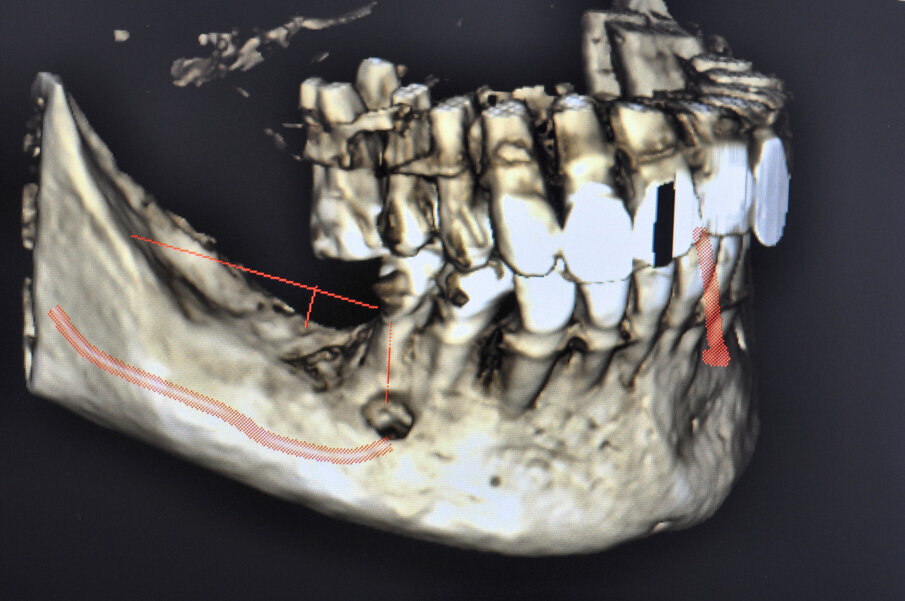

Figg. 1, 2_L’immagine clinica preoperatoria pone in evidenza un ampio difetto osseo sia orizzontale che verticale.